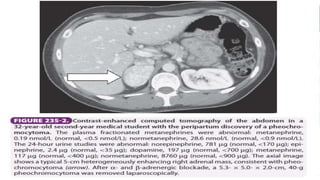

4- of cause:

- CT, MRI or sonography of abdomen